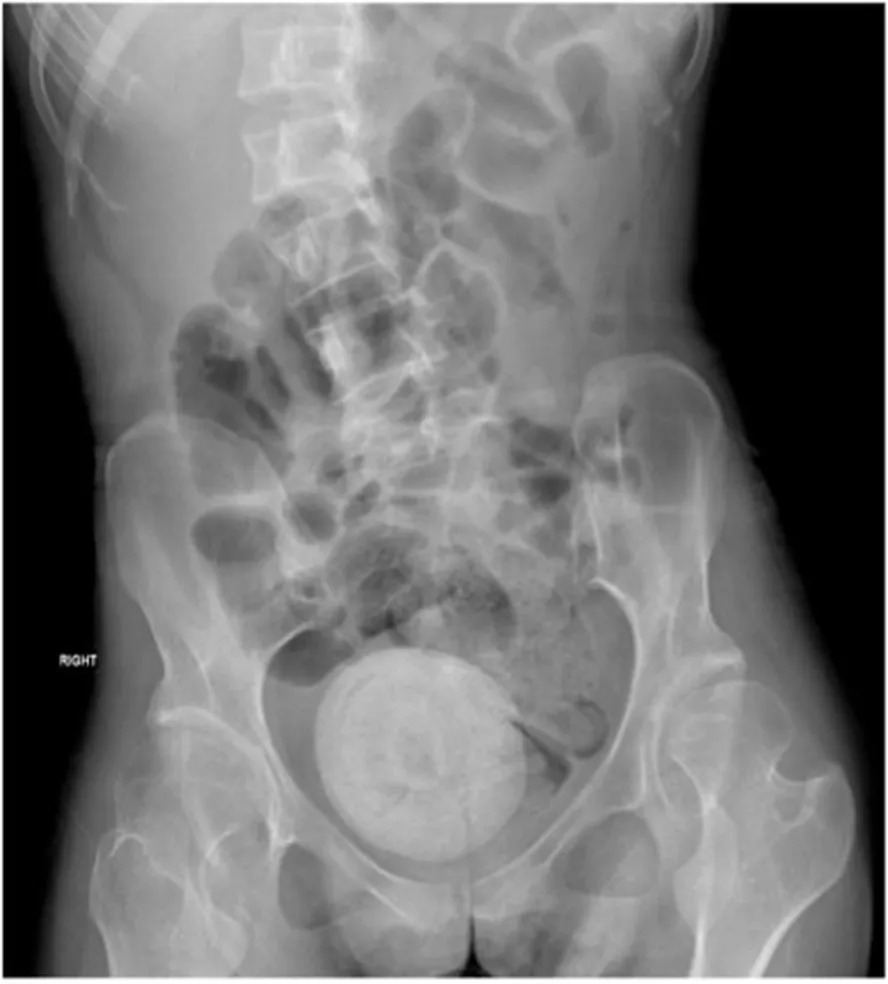

Os sintomas da mulher, que incluíam febre, calafrios, dores abdominais e vômitos, levaram-na ao pronto-socorro. Uma tomografia computadorizada revelou a pedra, que estava pressionando a bexiga da mulher e causando ainda mais perdas de urina.